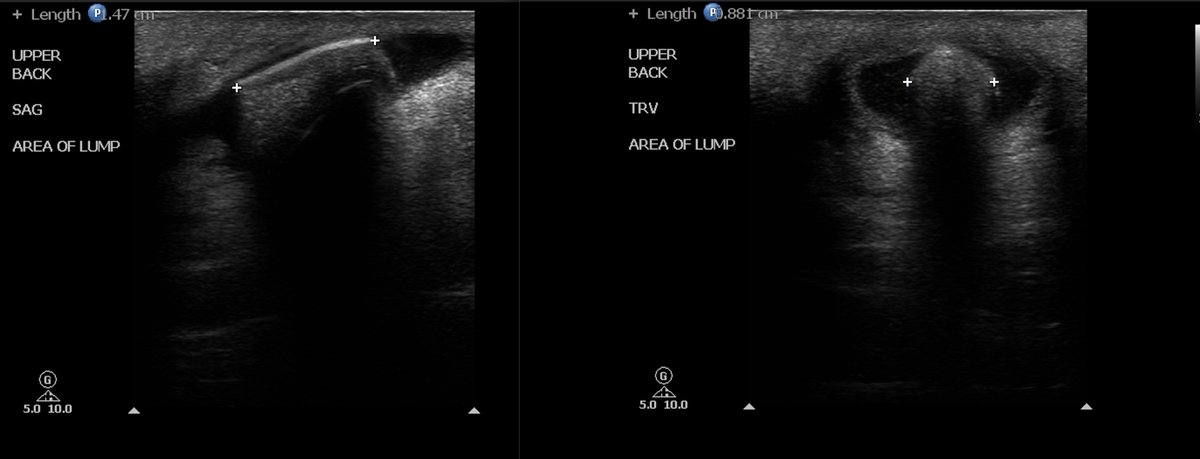

Retained wood piece in volar fingertip-22 days ago. X-rays neg. Diagnosed with felon. Standoff pad in sterile probe sheath used. Removed with alligator forceps.

Retained wood splinter with halo seen. Same case from above where removal shown. Standoff pad used.